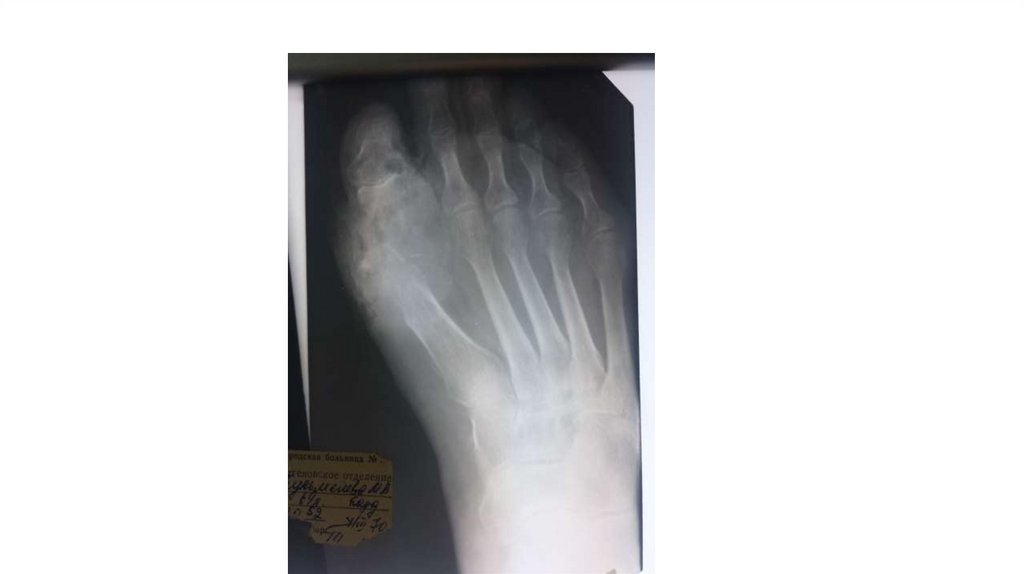

Воспалительные заболевания опорнодвигательного аппарата

«Воспалительные

заболевания опорнодвигательного аппарата»